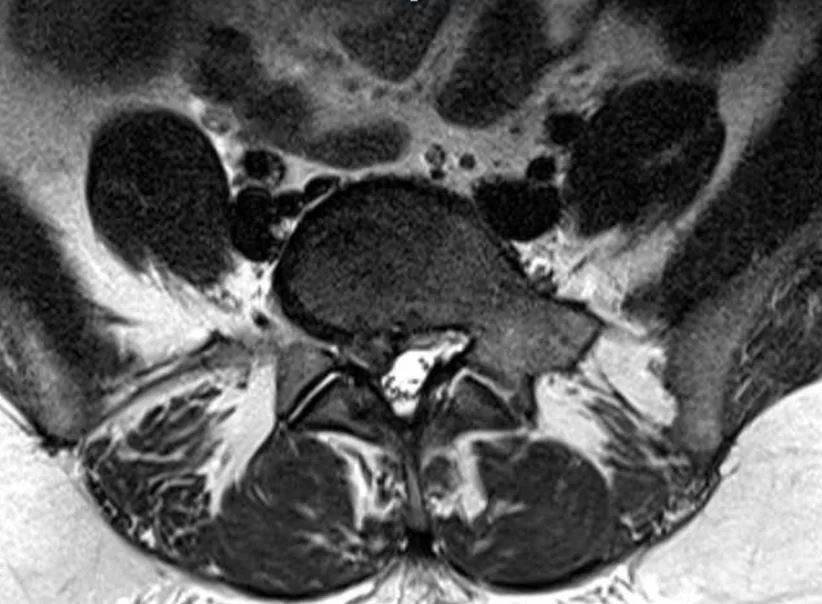

Πολλαπλά σβαννώματα (Νευρινώματα) οσφυϊκής μοίρας σπονδυλικής στήλης

Ασθενής άνδρας 75ετών με έντονο πόνο χαμηλά στη μέση, ιδίως κατά το κάθισμα. Επιπλέον, πόνος και στα δύο πόδια, ιδίως αριστερά, με έντονο μούδιασμα, το